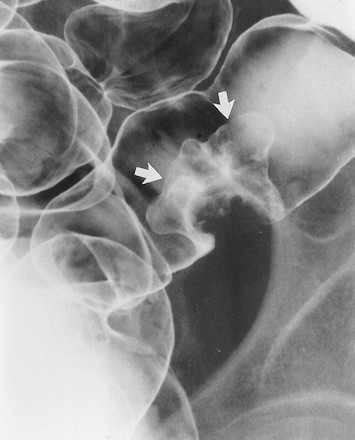

Các u tuyến có sự thay đổi lông nhung mao mức độ cao gọi là u tuyến lông nhung. Chúng là một dạng đặc biệt vì có nguy cơ thoái biến ác tính cao hơn các u tuyến ống hoặc u tuyến ống-lông nhung. Các u tuyến lông nhung có thể nhận ra trên các ảnh cản quang kép dưới hình các tổn thương polyp có bề mặt lưới hoặc nốt do baryt kẹt giữa các lông của khối u (Hình 7) [4].

Các khối u tuyến lông nhung có thể là các tổn thương chia thùy, phẳng, còn gọi là các tổn thương hình “tấm thảm”, chúng được mô tả là các thay đổi tinh vi ở bề mặt đại tràng, lồi rất ít hoặc không lồi vào lòng đại tràng. Kích thước trung bình của u 4 x 6 cm, thường mọc ở trực tràng, manh tràng, và đại tràng lên. Trên phim cản quang kép nhìn thẳng, các nốt to, nhỏ tụ với nhau thành mảng, phân cách nhau bởi các lưới mảnh đọng baryt (Hình 8) [5]. Khi nhìn nghiêng, tổn thương có bờ không đều, trái với bờ nhẵn của niêm mạc bình thường bao quanh.

Hình 7. Hình cản quang kép nằm ngửa cho thấy khối u tuyến lông nhung ở trực tràng. Tổn thương là khối dạng polyp (các mũi tên) với bề mặt nốt và lưới.